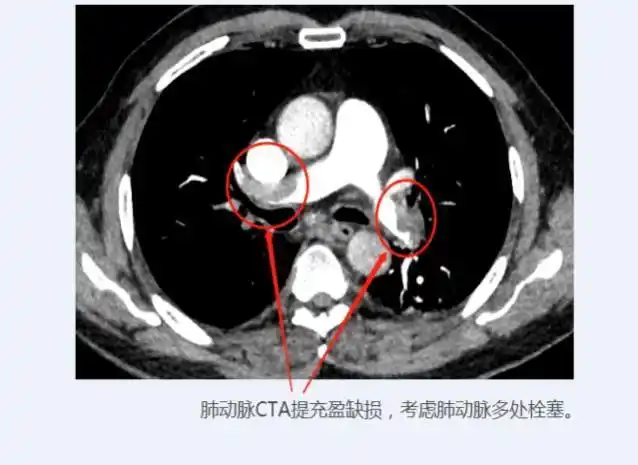

事不宜迟,许嗲嗲经绿色通道被快速送入放射影像科行肺动脉cta检查.